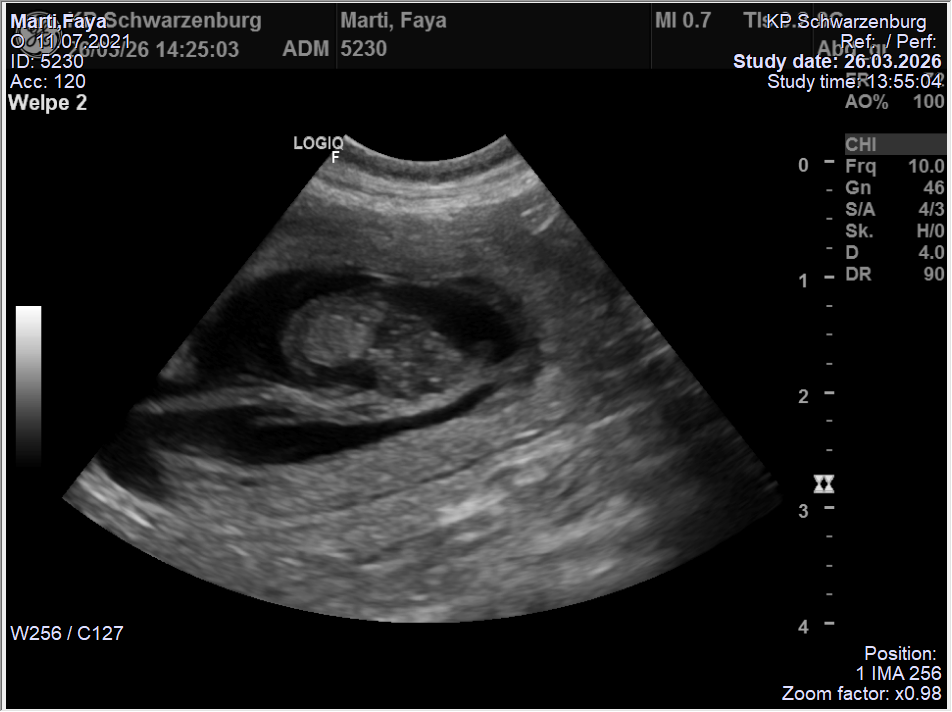

Nun heisst es weiter „brüten“ bis die Welpen Ende April auf die Welt kommen…